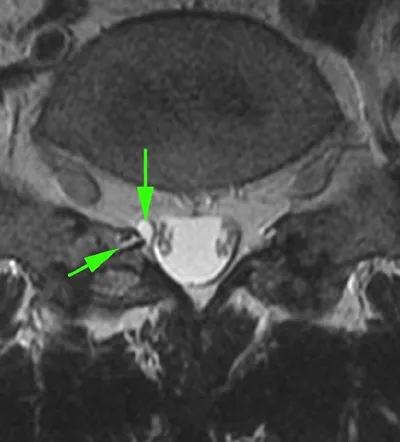

Рецидив атипичной спинальной менингиомы (первые снимки -2,5 года назад, после операции), за последний месяц - ухудшение состояния в виде нижнего парапареза и болей в спине. опухоль диффузная и муфтооб

Диагноз по одной картинке, все, как я люблю (надеюсь, что моя любовь уже передалась и вам).